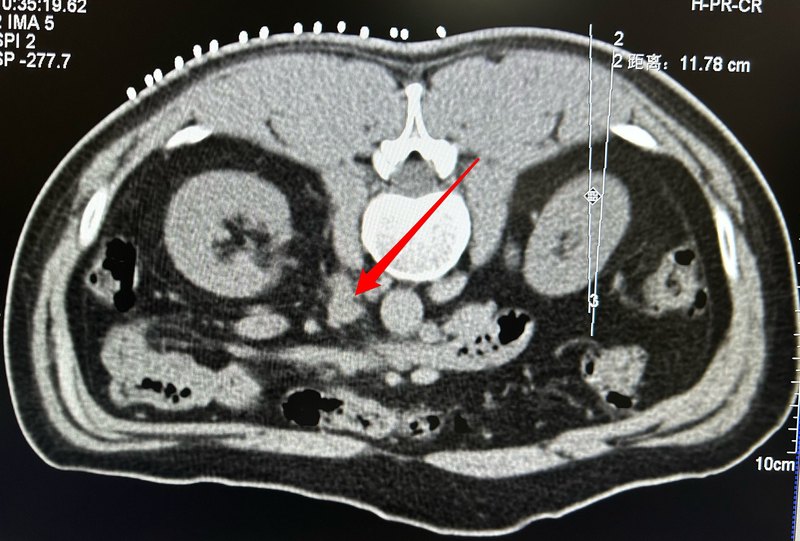

患者中年男性,肝癌腹膜后多發(fā)轉(zhuǎn)移,行粒子植入治療。點(diǎn)評(píng):腹膜后轉(zhuǎn)移瘤治療困難,該腫瘤被腎動(dòng)脈腎靜脈環(huán)繞,穿刺稍有誤差可能導(dǎo)致非常棘手的大出血,所以需要術(shù)者術(shù)前仔細(xì)閱讀增強(qiáng)ct片,穿刺時(shí)候分布進(jìn)針,確認(rèn)安全才穿刺到位及釋放碘125粒子。幸運(yùn)的是如果粒子植入位置準(zhǔn)確,此腫瘤一般可取得滿意的療效。所以粒子植入是腹膜后轉(zhuǎn)移瘤一個(gè)非常值得采納的治療手段。

深圳市人民醫(yī)院科普號(hào)2024年03月17日222